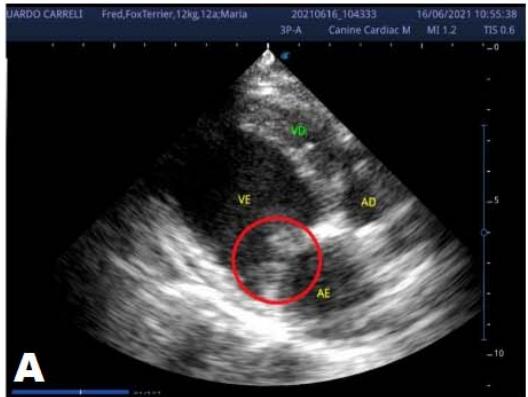

An echocardiogram (ECHO) (Figure 1) showed a thickened mitral valve and enlarged heart chambers. At first was prescribed Pimobendan PO at a dose of $0.25\mathrm{mg/kg}$ BID, continuous use, and requested to return in 30 days.

Figure 1: Echocardiogram 2021: Thickened/degenerated mitral valve (A); Observed in Doppler mode, significant mitral valve insufficiency (B); Hemodynamic assessment - Mitral regurgitation gradient: $3.45 \mathrm{~m} / \mathrm{s} / 47.68 \mathrm{mmHg}$; enlargement of left cardiac chambers; left ventricular diastolic dimension above normal limits was observed

In the reported, he was asymptomatic, and the echocardiographic examination showed enlargement of the left heart chambers, thickened and degenerated mitral valve (Figure 1), left ventricular diastolic dimension above normal limits. with normal systolic function parameters, characterizing systolic dysfunction. The thickening and degeneration of the mitral valve indicates its insufficiency, and the other changes represent diastolic dysfunction.